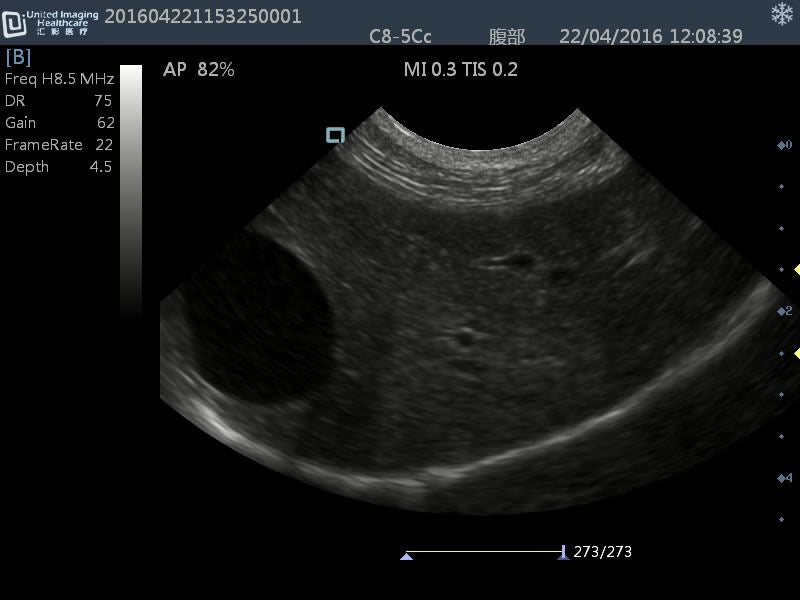

Micro-convex(R15): C8-5Cc

- Application: General small abdomen and cardiac

- Equine musculoskeletal and abdomens

- Number of element: 80

- Center frequency: 6.5MHz

- Working frequencies: 5 – 9MHz